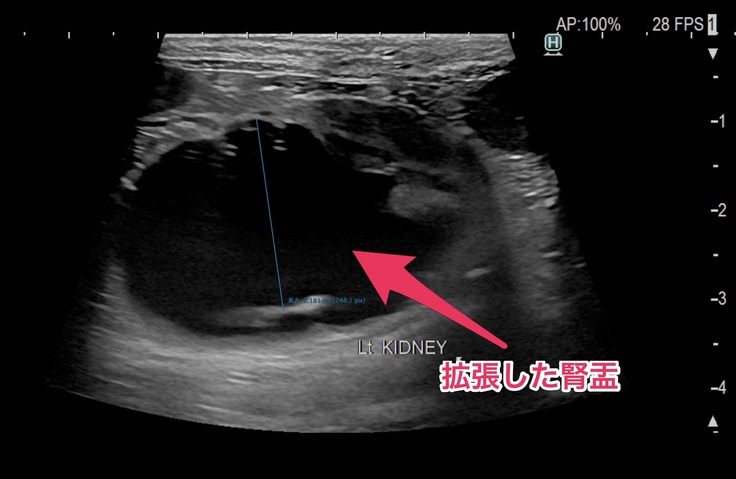

●左側の腎臓と腎盂が肥大して、ほとんど機能していない状態。(右側の腎臓と腎盂は正常)

ヨッチャンの腎臓の手術の内容ですがエコー検査で尿管が何かしらの原因で細くなっており、

CT検査とエコー検査の結果、ヨッちゃんの尿管が細くなっている原因は尿管結石ではなく①の手術は対象外となりました。尿管が細くなっている原因は先天性のものなのか後天性のものなのかは分からないけど、比較的腎臓に近い場所から尿管が細くなっているから②の手術で対応出来そうということで、たちまち腎臓と膀胱をつなぐ手術をしてもらうことになりました。

退院してからエコー検査をしたところ、手術後に本来なら腎臓の腎盂の大きさが小さくならないといけないけど腎盂の大きさが変わってないので(おしっこが溜まったままになっている)、術後に尿管にカテーテルを入れているので、尿管がカテーテルの太さに広がったまま、まだ元の細さに戻りきっていないことや、ほとんどない症例だけど尿管が太いまま戻っていないから膀胱から腎臓に逆流していることが考えられるので、尿の健康を維持するサプリを1日2回飲み続けてもらうことと、2か月に1回通院して検査をして経過観察をさせてほしいという話になりました。今後はサプリはかかりつけの病院で処方してもらって、検査や経過観察は専門の病院に通うことになりました。